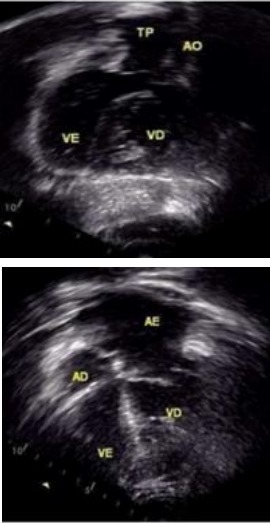

We describe a 35-year-old woman with left-sided invasive ductal carcinoma (HER2-, ER/PR+, Ki-67: 10%) and complex congenital heart disease: dextrocardia, congenitally corrected transposition of the great arteries, pulmonary stenosis, and ventricular septal defect. Pre-treatment evaluation included chest X-ray (Fig.1a), ECG (Fig. 1b), transthoracic echocardiography (Fig. 2), and cardiac MRI (Fig. 3). She underwent mastectomy, radiotherapy, and six cycles of docetaxel/cyclophosphamide chemotherapy. Cardiac function was monitored with serial echocardiograms and cardiac biomarkers (troponin, NT-proBNP). The patient developed heart failure with preserved ejection fraction (HFpEF) during chemotherapy. Clinical management with a loop diuretic and ACE inhibitor led to symptom resolution and clinical stabilization. The patient remained hemodynamically stable, with no drop in left ventricular ejection fraction.

Docetaxel and cyclophosphamide can be safely administered in dextrocardia, provided standard precautions are observed along with attention to altered cardiac anatomy. In cases with associated congenital heart disease, detailed cardiac imaging is crucial prior to chemotherapy.